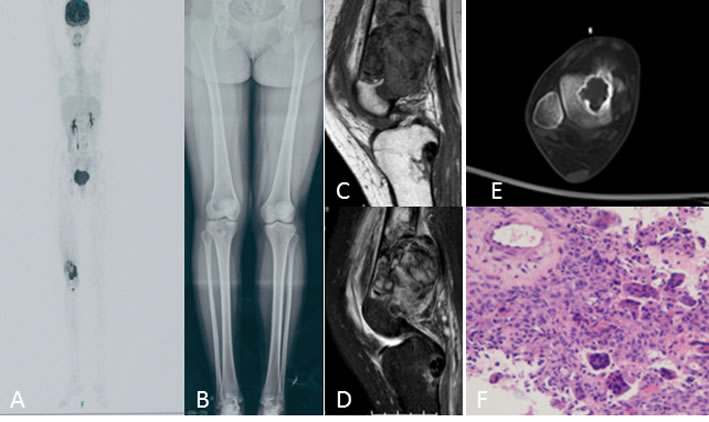

Figure 3: A 20-year-old woman with right knee swelling and pain. A. PET/CT shows right distal femur, proximal tibia, femur head, and talus with increased intake. B. Antero-posterior radiograph of the entire lower extremity shows multifocal osteolytic lesions. C., D. Knee MRI shows irregular, poorly defined soft tissue with T1 intermediate and T2 heterogeneous hyperintensity, extensive soft tissue edema in the distal femur and T1 hypointensity and T2 inhomogeneous low signal intensity in the proximal tibia. E. Talus CT shows osteolytic lesions with sclerotic ring margin. F. Histologic appearance of the giant cell tumor of the bone.

On radiographs (n = 14), 16 lesions manifested as geographic lucent lesions, and 1 lesion showed soft tissue density with stripe-like calcification (Figure 2B). Among these lesions, 9 lesions showed ring-like sclerosis (Figure 3B), 3 lesions showed patchy sclerosis (Figure 4E), and 4 lesions showed narrow transition without sclerosis (Figure 4B). Based on Campanacci et al’s grading system[23], 5 lesions were classified as grade III, 10 lesions as grade II, and 1 lesion as grade I. One lesion located in the calcaneus was treated with denosumab after one year, and a radiograph demonstrated shrinkage of the osteolytic zone and the formation of sclerosis in the center of the lesion and adjoining bone cortex (Figure 1D-1E). Four lesions showed increased sclerosis in the center and outer margin after six months.

On CT scanning (n = 13), 13 lesions showed marrow replacement by tissue with homogeneous attenuation, with homogeneity in 1 lesion. Nine lesions more clearly demonstrated sclerotic margins or patchy sclerosis (Figure 1A-1B). Three lesions showed a narrow transition without sclerosis. Eight lesions showed cortical discontinuity, and 5 lesions showed soft tissue mass throughout the bone cortex. Two lesions were treated with denosumab after four months; CT showed ring-like sclerosis around the outer margin (Figure 4H-4I) and increased sclerosis in the center of the lesion (Figure 4J-4K).

On MRI (n = 8), 2 lesions showed marrow replacement by homogeneous tissue, and 6 lesions showed marrow replacement by heterogeneous tissue on T1-weighted images. Two lesions had intermediate signal intensity (similar to that of the muscle), and 3 lesions showed predominately intermediate signal intensity with patchy or stripe-like low signal intensify (Figure 5C); 2 lesions showed mildly higher intensity than muscle, and 1 lesion showed low signal intensity on T1-weighted MR images (Figure 4F). On T2-weighted MR images, the signal intensity was heterogeneous in 6 lesions and homogeneous in 2 lesions. Five lesions showed predominately high signal intensity (similar to that of fat) with patchy or stripe-like low signal intensity (Figure 5D), and 1 lesion showed higher signal intensity than that of fat; 2 lesions showed homogeneous high signal intensity (Figure 4C). One lesion subjected to contrast enhancement showed obvious enhancement. In addition, cortical destruction with an associated soft tissue mass and extensive edema was seen 3 lesions.

PET-CT (n = 2) showed increased uptake of 18F-PDG, with homogeneity in 5 lesions and heterogeneity in 1 lesion (Figure 3A).